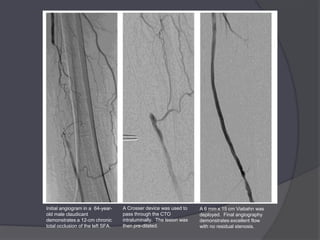

Initial angiogram in a 64-year-    A Crosser device was used to     A 6 mm x 15 cm Viabahn was

old male claudicant                pass through the CTO             deployed. Final angiography

demonstrates a 12-cm chronic       intraluminally. The lesion was   demonstrates excellent flow

total occlusion of the left SFA.   then pre-dilated.                with no residual stenosis.